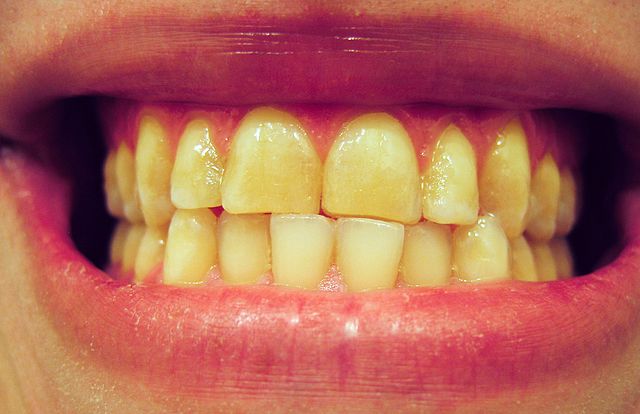

La onicofagia también puede tener efectos negativos en la salud bucal y provocar diversos problemas dentales y en las encías. Morderse las uñas continuamente puede llevar al desgaste del esmalte dental que es la capa protectora más externa de los dientes. Su desgaste puede aumentar la sensibilidad dental y hacer que los dientes sean más susceptibles a las caries. También se pueden producir microtraumatismos en los dientes, especialmente en los incisivos, lo que con el tiempo debilita las piezas. Cuando una persona se muerde las uñas, los dientes a menudo chocan entre sí, y ese gesto repetitivo puede provocar astillamiento dental.